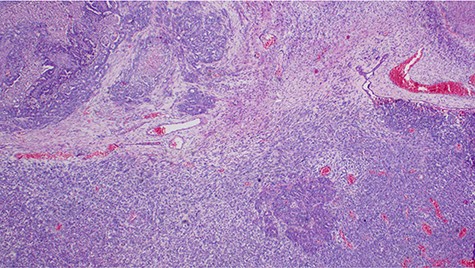

p53 immunohistochemistry highlighting tumor cell positivity on both epithelial and stromal elements, ×40.

Explorative laparotomy was done, intra-operatively, and a complex cystic left ovarian mass was found with extensive omental and uterine carcinomatosis seedlings. The liver and spleen were normal. Omentectomy, total abdominal hysterectomy and bilateral salpingo-oophorectomy was done and the samples (Fig. 3) were taken for histopathology. The histopathology results revealed the presence of malignant mixed Müllerian tumor of the ovaries with metastasis to the omentum (Figs 4, 5). The rest of uterus was essentially unremarkable. The tumor cells were strongly positive for p53 immunohistochemistry (on both epithelial and stromal components) (Fig. 6). Furthermore, the epithelial component of the tumor was positive for epithelial membrane antigen immunohistochemistry, whereas stromal element was positive for vimentin.

Malignant mixed Müllerian tumor of the ovary is a rare tumor that accounts for ~1% of all ovarian cancers [1, 2]. These tumors are typically large, ranging from 10–20 cm in diameter; our patient’s tumor was 15.6 × 7.1 × 6.1 cm (Fig. 3). The presence of an intimate admixture of malignant epithelial and stromal elements (Figs 4, 5) is the morphological characteristic feature of this tumor. The epithelial element is most commonly a high-grade serous or endometrioid carcinoma, but can be of any of the surface epithelial cell types of ovarian tumors. The stromal component usually contains sheets of hyperchromatic rounded to spindled cells with marked nuclear atypia and a high mitotic index (Fig. 5). Immunohistochemical stains for epithelial markers are often positive in the sarcomatous component, as it has been observed in the index case (Fig. 6), and their behavior and patterns of spread are similar to high-grade serous carcinomas [3–5].